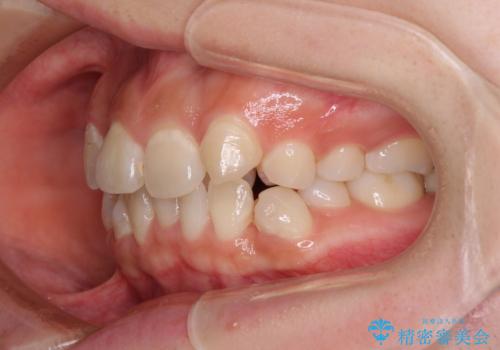

見えないほど重なっている前歯 抜歯矯正でスッキリとした歯並びに

これほど顕著に裏側に隠れいてる歯ですと、仕上がったときに両隣の歯と軸に差が認められることが多いのですが、殆ど違和感のない歯並びを達成することができました。